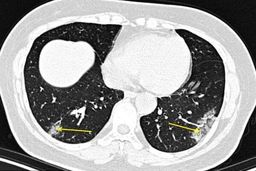

تشخیص سریع ابتلا به کرونا با سی تی اسکن

خبرمهم: گروهی از محققان در آمریکا متوجه شده اند سی تی اسکن ریه ۴ روز زودتر ابتلای فرد به ویروس کرونا را نشان می دهد.